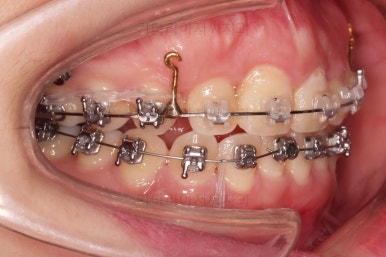

미니스크류를 적절히 사용해서 부정교합도 맞추고 입매도 약간 들어가게 혹은 너무 들어가지 않게 조절해 주고요.

치열의 경사 등등도 조절해 줍니다.

부산부정교합이긴 하지만 애초에 입매가 많이 나쁘진 않았기 때문에 자칫하면 입이 너무 들어갈 수 있어 중간중간 환자분과 상의하여 너무 들어가지 않게끔 조절해 줍니다.

적절하게 틈도 다 모아주고요.

디테일을 정리하고 마무리를 하게 됩니다.